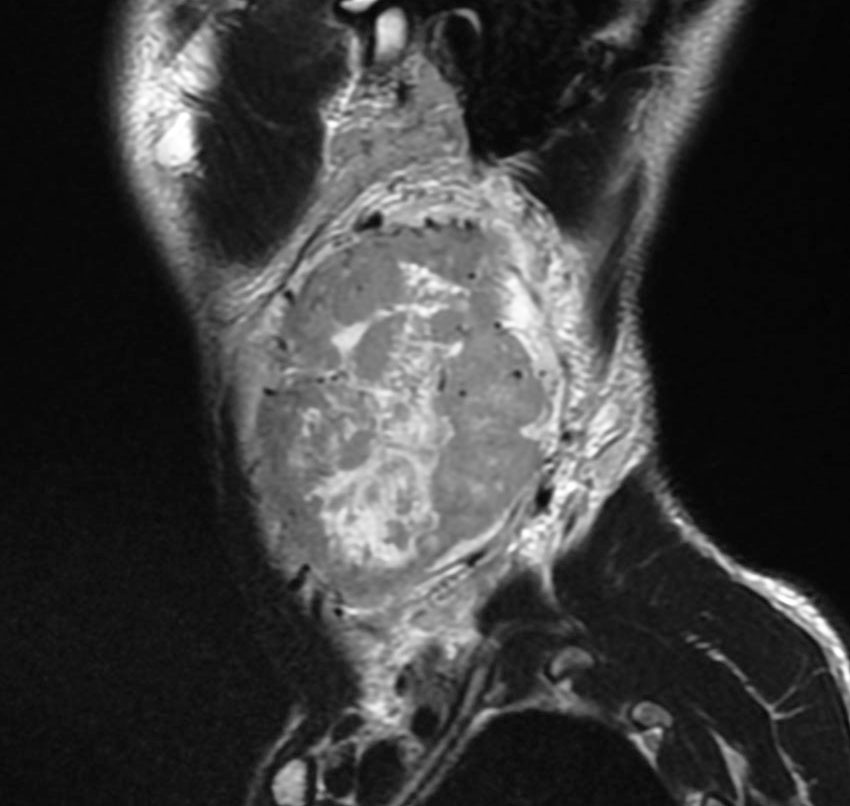

耳の聞こえと飲み込みが悪くなって発症(難聴と嚥下障害)した20代の患者さんのグロームス腫瘍 jugular paragangliomaです。左の頚動脈撮影 CAGでは,頸部の腫瘍におされて内頚動脈が前方に屈曲しています。外頚動脈から多くの血管が流入して血管腫のように濃い腫瘍陰影がみえます。右側の椎骨動脈撮影 VAGでは,頚静脈孔から頭蓋内の小脳延髄角部まで伸びた腫瘍が染まります。頭蓋内はPICAから頸静脈球と頸部には椎骨動脈の筋肉枝からの腫瘍血管がみられます。

頸部から頸静脈球を抜けてS上静脈洞内に入ります。これはクラスCかDか迷うところです。ちょっと難しい。またこのサイズでは,迷走神経と舌咽神経の機能を温存することができません。延髄方向へ伸展していますし年齢が若いので手術せざるを得ないものでした。

この腫瘍は放射線治療で制御できるものではないでしょう。手術で全摘出できて10年以上再発はありません。嚥下障害と強い嗄声が残りましたが,働いて社会生活はできています。